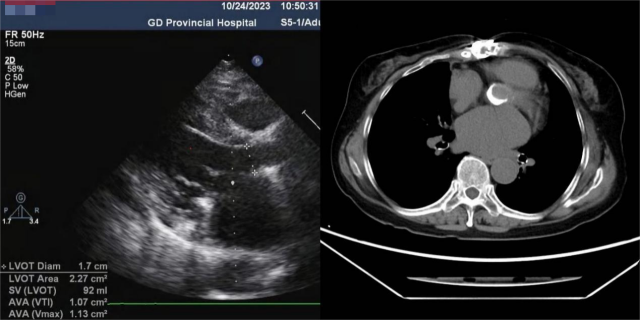

但是,郭惠明团队为陈云检查后发现,她的血管翳巨大且覆盖的范围广,完全清除的难度较大,只能再度通过置换主动脉瓣的方式来解除梗阻。

郭惠明分析,陈云之前植入过2次机械瓣膜,等于是在血管内“层层套娃”。如果这次继续为她植入新的瓣膜,她的血管将会更狭窄,同样影响血液流动。

“如果要增加患者的血流,就需要先扩大她的主动脉瓣环,才能换上更大的主动脉瓣膜。与此同时,还需要拓宽她的左心室血液流出道。”郭惠明说。